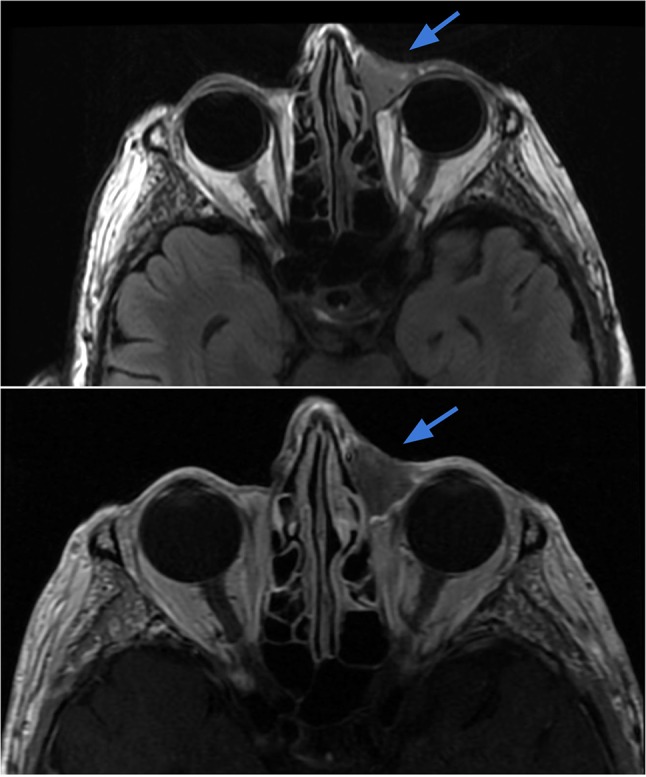

Case 5.

Rhabdomyosarcoma of the left orbit in a 28-year-old female with blurry vision, proptosis and orbital pain with movement. Axial T2-weighted (top left) and T1 post-contrast (top right) images demonstrate a T2 heterogeneously hyperintense mass with avid enhancement within the left posterior orbit (blue arrows), with extraconal components eroding the medial orbital wall and extending into the nasal cavity. The mass exhibits bright signal on DWI (bottom left) and dark signal on ADC (bottom right) reflecting low diffusivity in keeping with the highly cellular tumor (red arrows)